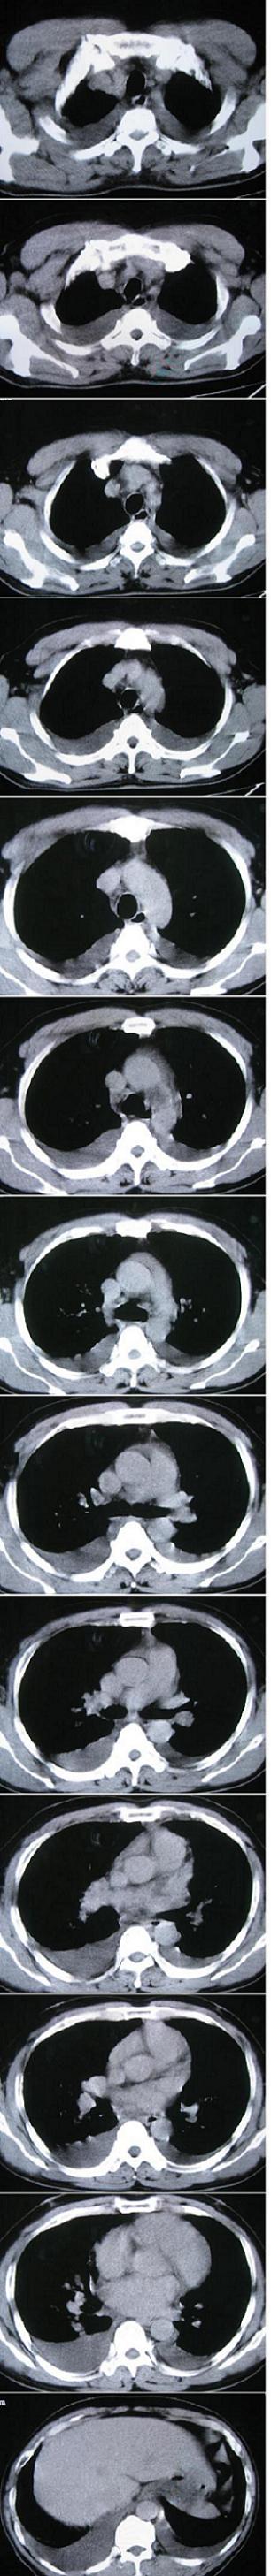

男,36岁,胸闷气喘三天来诊

考虑---肺水肿,双侧胸水。

双肺弥漫性病变 支持肺水肿 双侧胸水

支持  肺水肿,双侧胸腔积液。心包少量积液。注意心功能检查

心衰\\肺水肿\\胸积液

典型肺泡性肺水肿伴双侧胸腔积液。

典型肺泡性肺水肿伴双侧胸腔积液,病因呢?

肺泡性肺水肿并双侧胸腔积液。